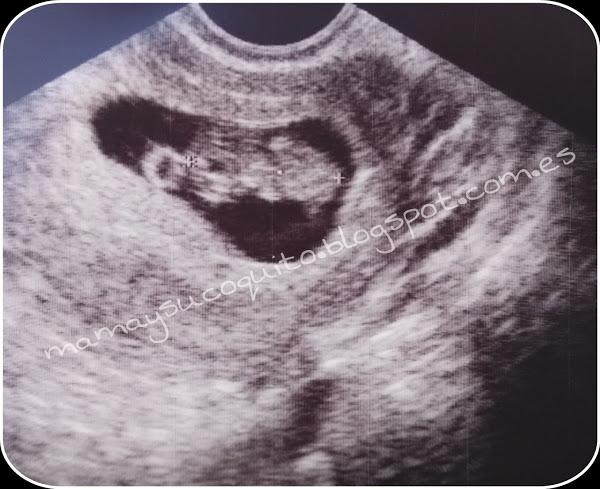

En la siguiente visita vimos los resultados de los análisis de sangre y orina que dieron perfectos y volvimos a ver "la carita" al bebé. La ecografía que os muestro es de 9-10 semanas de gestación. Y ya me recordaban que debería volver a ponerme la vacuna de antiglobulina por el grupo y rh sanguíneo, pero eso no será hasta las 28 semanas.

Ecografía 9 semanas.